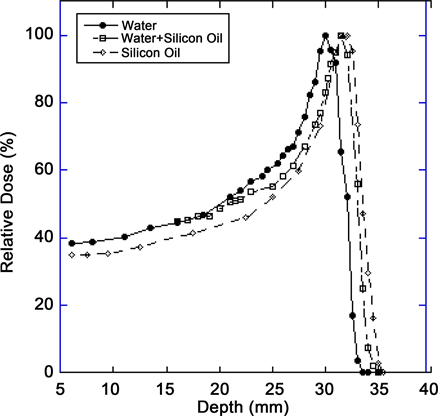

The measured data as shown in Figure 4 and Table 2 reveal that un-modulated

Figure 4. Comparison of the range of a 67.5 MeV proton beam in the central axis as measured in water, water + oil and in silicone oil.

Bragg peak has a penetration of 30 mm in water at the iso-center as compared to 32 mm range in silicone oil. By placing 1 cc of silicone oil in front of water tank, the range of proton beam is 31.5 mm. The ratio of range for water/silicone (oil +water) and water to silicone oil is 0.95 and 0.9375 respectively. The width of the depth dose curve at (FWHM) is 9 mm in water, 10 mm in water + silicone oil and 11 mm in silicone oil. The peak/plateau ratio of the depth dose is 3.1. The distal penumbra measurements (from 90% to 20%) were 1.1 mm for water, 1.4 mm for water + silicone oil and 2 mm for silicone oil, respectively.

In our paper we build on this initial work to provide a comprehensive description of the effect of silicone oil on proton beam parameters, particularly with an experimental design to more closely simulate an eye filled with silicone. Thus, we made the measurements of our proton beam in a tank of silicone oil itself (simulating a silicone-filled eye) and compared the beam parameters to that in a water tank (simulating a “normal” eye) as well as water + silicone oil as previously described. The results indicate that the shape of the Bragg-peak is affected in silicone oil and range of the beam is increased by 2 mm in silicone oil and 1.5 mm in water + silicone oil. This is congruent with initial results from Weber et al. [15] . The width of the depth dose curve at (FWHM) is 9 mm in water, 10 mm in water + silicone oil and 11 mm in silicone oil. The distal penumbra measurements (90% to 20%) are 1.1 mm for water, 1.4 mm for water + silicone oil and 2 mm for silicone oil, respectively.